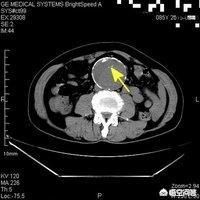

4.PET/CT検査

この検査は、より身近なものかもしれないが、非常に高価で、通常8,000ドル以上する。主に体内のがん病変の検出に使われ、患者のてんかん病変の判定にも使われる。

1.PET-CT(ポジトロンCT):

現在、PET-CTは約1万ドルで、より高価な検査とされ、払い戻しはできない。PET-CTは、陽電子放出核種を使ってグルコース、脂肪酸、アミノ酸、水などを標識し、陽電子スキャナーを使って体内の化学画像を得る原理に基づいており、主に早期の腫瘍の診断に用いられ、現在最も感度の高い検査方法である;

(1) PET/CT

PET/CTは非常に高価な検査で、全身PET/CT検査は8,000~10,000ドルかかり、健康保険で償還されません。PET/CTは、腫瘍の部位、浸潤の程度、遠隔転移の有無などを評価する非常に重要な検査です。PET/CT検査を健康診断に使用できるかという質問もあるが、それは不可能である。なぜなら、PET/CT検査は高価であり、偽陽性が出やすいからである。また、PET/CT検査は放射性であり、ルーチンの健康診断には推奨されないからである。